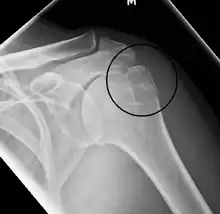

Fracture of the greater tuberosity of the humerus -

Multi-fragmented, or comminuted fracture of the proximal humerus with involvement of the greater tuberosity -